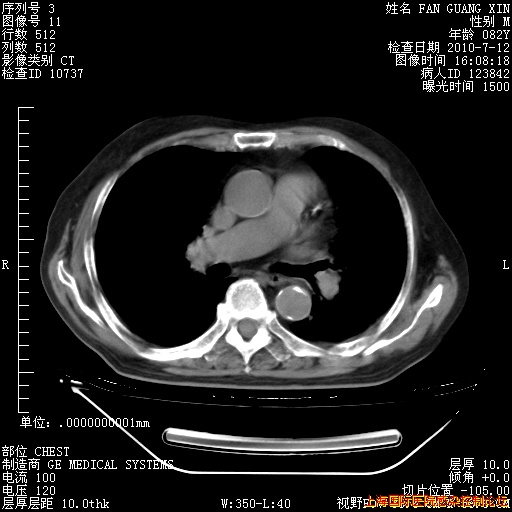

6月12日纵膈窗

整整相隔30天的肺部CT好像有所好转啊。甲强龙减量第3天,需要观察体温。